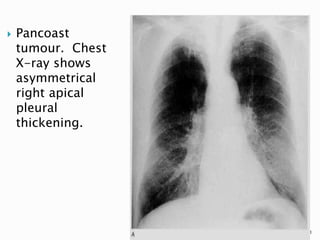

 Cancers arising in the lung apex, known as

superior sulcus or Pancoast tumors (usually

squamous cell carcinomas), are a distinct

subgroup because of their characteristic

location and constellation of symptoms.

 Radiographic findings can be quite subtle

and are frequently obscured by, or

misinterpreted as, overlying

musculoskeletal structures, brachiocephalic

vessels, or benign pleural thickening.

48

 Findings suggestive of malignancy include

an apical cap >5 mm, asymmetry of apical

caps >5 mm, an apical mass, and adjacent

bone destruction.

 Clinical symptoms of arm pain and a

Horner's syndrome are classically

associated with a Pancoast tumor.

 Pancoast

tumour. Chest

X-ray shows

asymmetrical

right apical

pleural

thickening.

51